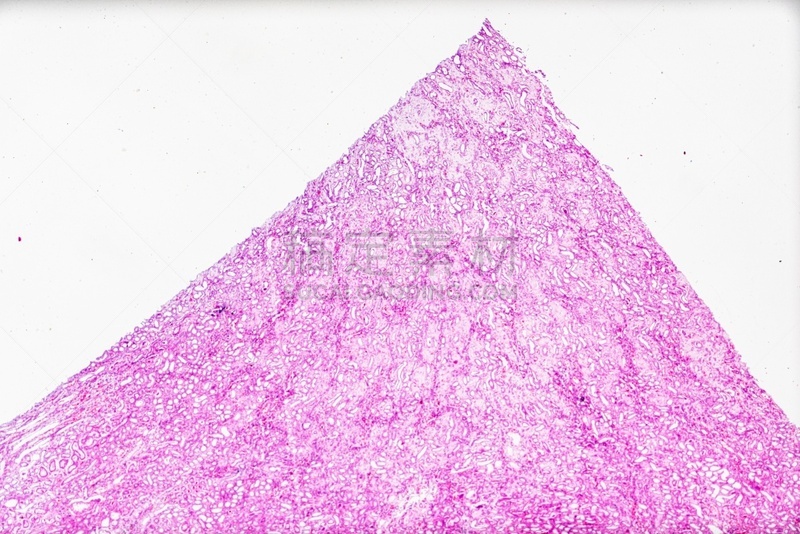

显微镜下的小鼠肾脏详情